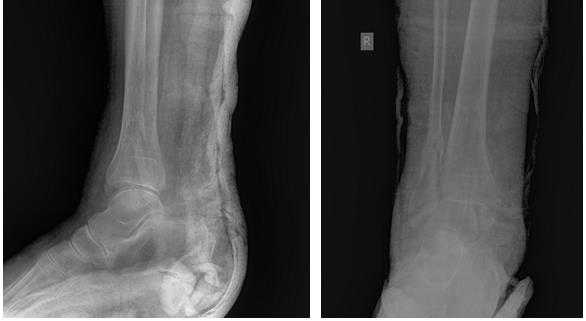

Пациент М. 1980 г.р., травму получил при падении на стопы с высоты 1,5 метра. Лечился по месту жительства (в травмпункте районной больницы) консервативно в гипсовой повязке в течение 14 дней. Консультирован в травматологическом отделении ФГБУ «УНИИТО им. В.Д. Чаклина» Минздрава РФ, предложено оперативное лечение. При поступлении кожные покровы стопы чистые, без признаков воспаления и сдавления тканей. Стопа отечна, уплощена. На рис. 1 представлены рентгенограммы пациента. Прооперирован через 2 недели после травмы. Операция состоит из двух этапов. Первый этап заключается в наложении дистракционного аппарата. Проводятся две спицы 1,8 мм во фронтальной плоскости: первая через нижнюю треть диафиза большеберцовой кости, вторая через бугор пяточной кости (рис. 2). Спицы фиксируются в дистракционном аппарате, выполненном из двух полуколец, соединенных между собой двумя телескопическими тягами. Особое расположение полуколец, фиксация спиц на концах полуколец, крепление кронштейнов для телескопических тяг обеспечивает тракцию пяточной кости в необходимом направлении с использованием минимального количества спиц и внешних опор при сохранении необходимого поля обзора для проведения рентгенологического и визуального контроля репозиции и фиксации. Второй этап - закрытая элевация импрессированной суставной поверхности и окончательная репозиция пяточной кости. Через разрез длиной до 1 см по латеральному краю ахиллова сухожилия (рис. 3) в месте его прикрепления к пяточной кости под соответствующий фрагмент подводится элеватор (рис. 4), манипуляцией которым устраняется смещение и выполняется провизорная фиксация спицами 1,5 мм (рис. 5). При сагиттальном раскалывании суставной фасетки целесообразно проведение одного-двух винтов субхондрально (рис. 6). Стержень вводится с дорзальной поверхности пяточной кости по ее оси через разрез до 2 см по предварительно сформированному остеотомом каналу (рис. 7, 8). Далее через проколы кожи с помощью кондуктора (рис. 9) выполняется запирание винтами с латеральной поверхности, внешнее устройство демонтируется. Достигнуто удовлетворительное стояние отломков (рис. 10).

Рис. 1. На рентгенограмме левой стопы в прямой и боковой проекциях определяется оскольчатый внутрисуставной перелом левой пяточной кости